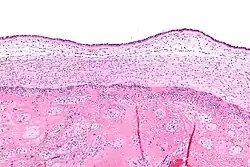

Chorioamnionitis is diagnosed from a histologic (tissue) examination of the fetal membranes.[12] Confirmed histologic chorioamnionitis without any clinical symptoms is termed subclinical chorioamnionitis and is more common than symptomatic clinical chorioamnionitis.[2]

Infiltration of the chorionic plate by neutrophils is diagnostic of (mild) chorioamnionitis. More severe chorioamnionitis involves subamniotic tissue and may have fetal membrane necrosis and/or abscess formation.[1]